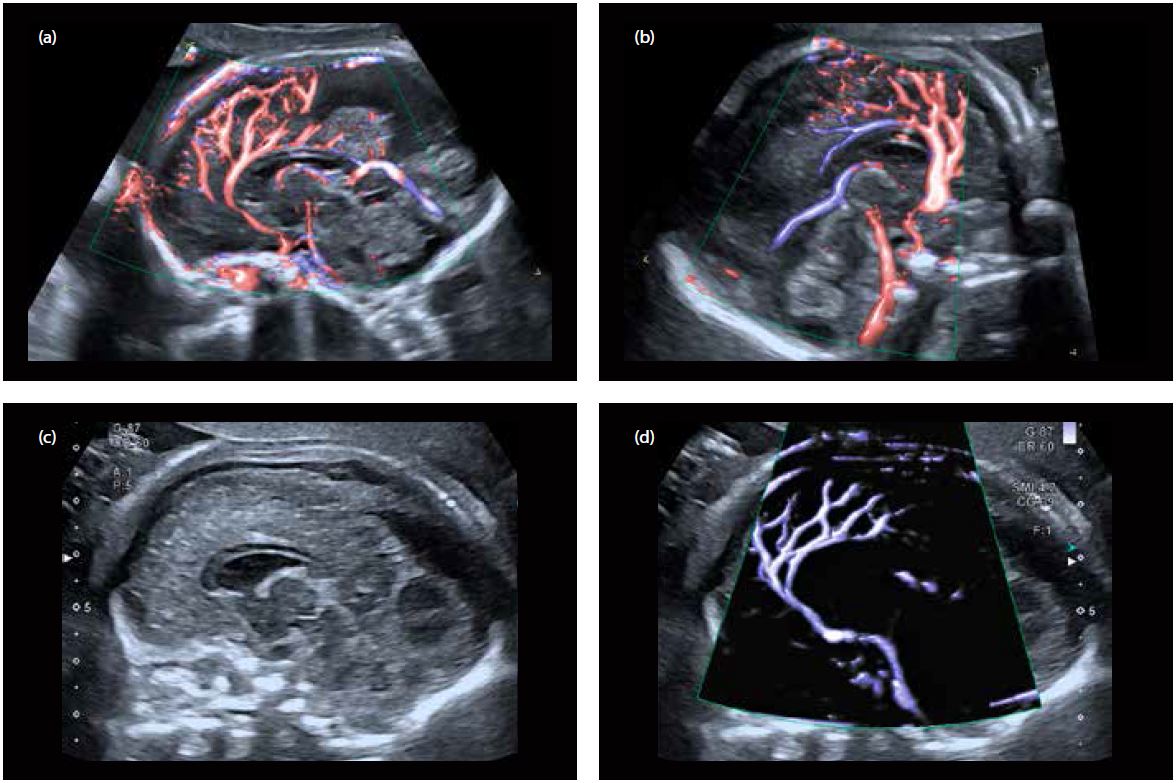

Зображення, отримані під час дослідження того ж плоду, демонструють використання різноманітних кольорових доплерівських методів, доступних на платформі Aplio. SMI виявився неймовірно корисним не тільки для точної візуалізації головних церебральних артерій і вен, але й для візуалізації судинних гілок дуже малого діаметру з надзвичайною точністю та з дуже високою частотою кадрів (мал. 2).

Малюнок 2 Нормальний мозок плоду на 20-у тижні гістаційного віку:

a) та b) Сагітальні зрізи головного мозку плода за допомогою ADF; видно перікаллозальна артерія та її гілки, а також вена Галена

c) та d) Подвійне вікно з зображенням серединного сагітального зрізу з візуалізацією мозолистого тіла та васкуляризацією за допомогою SMI